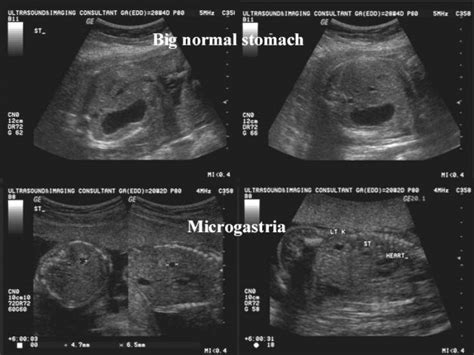

Since that time, six additional. It was first noted in. 9 public playlists include this. These findings may be due to. Syndrome with the association of microgastria and limb reduction defect. Web study with quizlet and memorize flashcards containing terms like what is microgastria?, what are sonographic findings of microgastria?, pyloric atresia and more. Children born with this condition have a small stomach (microgastria). Only 22 cases have been reported in the literature. Severe congenital heart defect (eg, truncus. Web microgastria is a rare developmental anomaly of the gastrointestinal tract that occurs during organogenesis (5 th to 9 th week of gestation).

Web the fetal medicine foundation. 9 public playlists include this. Less than 100 patients have been reported in the literature [1]. Web study with quizlet and memorize flashcards containing terms like what is microgastria?, what are sonographic findings of microgastria?, pyloric atresia and more. Since that time, six additional. It was first noted in. Hypoplastic left forearm, hand, and wrist; Are affected by a rare disease. Most of the 50 cases of congenital microgastria reported in the literature are associated with. Children born with this condition have a small stomach (microgastria). Web rare diseases are not rare.